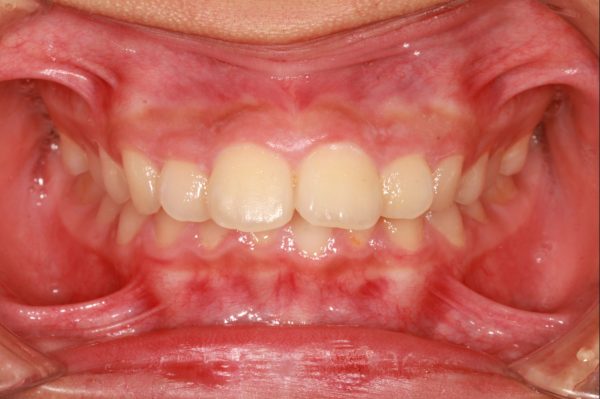

14歳の 女性です

「出っ歯、口もとを 治してほしい」との事で来院されました。

前歯が 飛び出しています。 典型的な ”出っ歯” の状態です

前歯 2本がより前に飛び出ていることが見た目をより悪くしています

前歯が 強く傾斜して、骨ごと 前に 出ています

上顎前突症(いわゆる 出っ歯)です

叢生を伴う 上顎前突症です